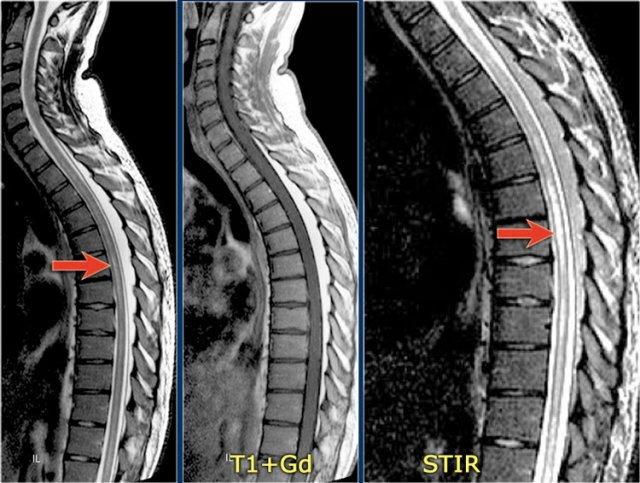

Hình ảnh bên trái của một trẻ em nhập viện với viêm thần kinh thị giác một bên.

Hình ảnh não hoàn toàn bình thường.

Tiếp tục xem MRI cột sống.

Những bệnh nhân có một đợt viêm thần kinh thị giác hoặc viêm tủy và có kết quả xét nghiệm NMO-IgG dương tính có nguy cơ cao tiến triển thành toàn bộ phổ bệnh NMO.

Một tháng sau, trẻ này nhập viện với bệnh tủy cắt ngang cấp tính, tức là các triệu chứng hai bên.

Hình ảnh cho thấy tín hiệu bất thường trong tủy sống kèm phù nề và ngấm thuốc nhẹ.

U tế bào hình sao (astrocytoma) hoàn toàn có thể biểu hiện với hình ảnh tương tự, tuy nhiên dựa vào tiền sử viêm thần kinh thị giác và bệnh tủy cấp tính, chúng ta không nghĩ đến khối u.

Trường hợp này được xác định là NMO và xét nghiệm Ig cho NMO dương tính.